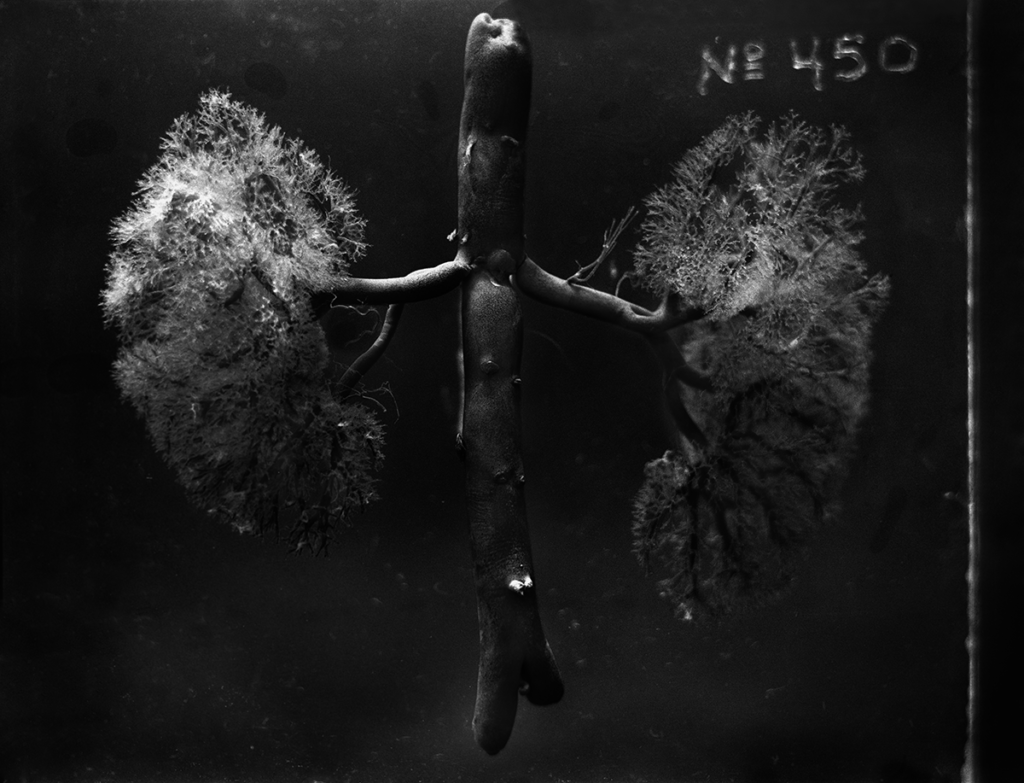

series: OJardim

year: 2014

suport: black and white 6×7 medium format film, Giclée on

Hahnemühle Photo Satin 310gsm

edition: 1/6 + 3 Ap

size: 55x72cm

year: 2014

suport: black and white 6×7 medium format film, Giclée on

Hahnemühle Photo Satin 310gsm

edition: 1/6 + 3 Ap

size: 55x72cm

The OJardim series was made using a large-format camera (5×7 inches) and medium format (6×7 cm) and a fifth lens built by Daniel Malva. This lens uses the glass’s elements at a better quality compared to other lenses that Malva has built. The result is the ability to show more details of the human anatomy in his pieces.